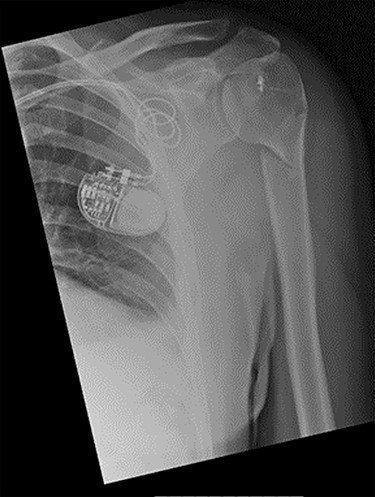

An X-ray of the left shoulder was performed, which revealed acceptable positioning of the fracture. Following a discussion with the patient, a mutual decision was made to manage the injury non-operatively and he was discharged with a collar and cuff sling. Subsequent clinical and radiological review at 1 week and 2 weeks post-injury showed the soft tissues to be healing well and the fracture to be well-positioned (Figs 5 and 6).

Antero-posterior view X-ray taken 2 weeks post-injury showing acceptable positioning of the fracture.